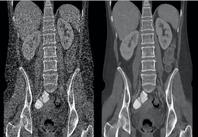

Veo image demonstration

The image at left demonstrates filtered back projection (FBP) image reconstruction using conventional CT imaging, and, at right, an image reconstruction using Veo. Veo, developed by Purdue University, University of Notre Dame and GE Healthcare, is a new CT scanning technology that enables physicians to diagnose patients with high clarity images at previously unattainable low radiation dose levels. (Image provided by Purdue University)